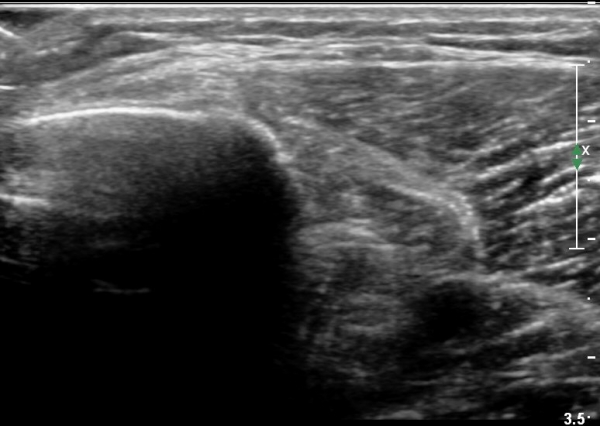

[¹«¸­] °æ°ñ ÇǷΰñÀý ÃÊÀ½ÆÄ¼Ò°ß(sonographic findings of stress fracture of tibia)

¿ìÃø ¹ß¸ñ°ú ¾Æ·§´Ù¸® ÅëÁõ(±â°£ 2ÁÖ)

±º´ë¿¡ ÀÔ´ëÇÏ¿© ÈÆ·ÃÀ» ¹ÞÀº º´·ÂÀÌ Àִ ȯÀÚ´Â ¾à 2ÁÖ ÀüºÎÅÍ ¹ß¸ñ ºÎÀ§ÀÇ ÅëÁõÀÌ ÀÖ´ø Áß

ÃÖ±Ù¿¡´Â ¹ß¸ñ À§ ¾Æ·§´Ù¸®¿¡ ÅëÁõÀÌ ¹ß»ýÇÏ°í ½ÉÇÏ°Ô °ÉÀ¸¸é ½ÉÇØÁö´Â ¾ç»óÀÓ

¾Æ·§´Ù¸® Áß°£ ºÎÀ§¿¡ °æ¹ÌÇÑ ¿¬ºÎÁ¶Á÷ ºÎÁ¾ÀÌ °üÂûµÇ°í ¾à°£ÀÇ ±¹¼ÒÀû ¾ÐÅëÀ» º¸ÀÓ.

ÃÊÀ½ÆÄ °Ë»ç

¹Ì¼¼ÇÏ°Ô ¿¬ºÎÁ¶Á÷ ºÎÁ¾°ú °¡°ñ Çü¼ºÀÌ °üÂûµÊ.